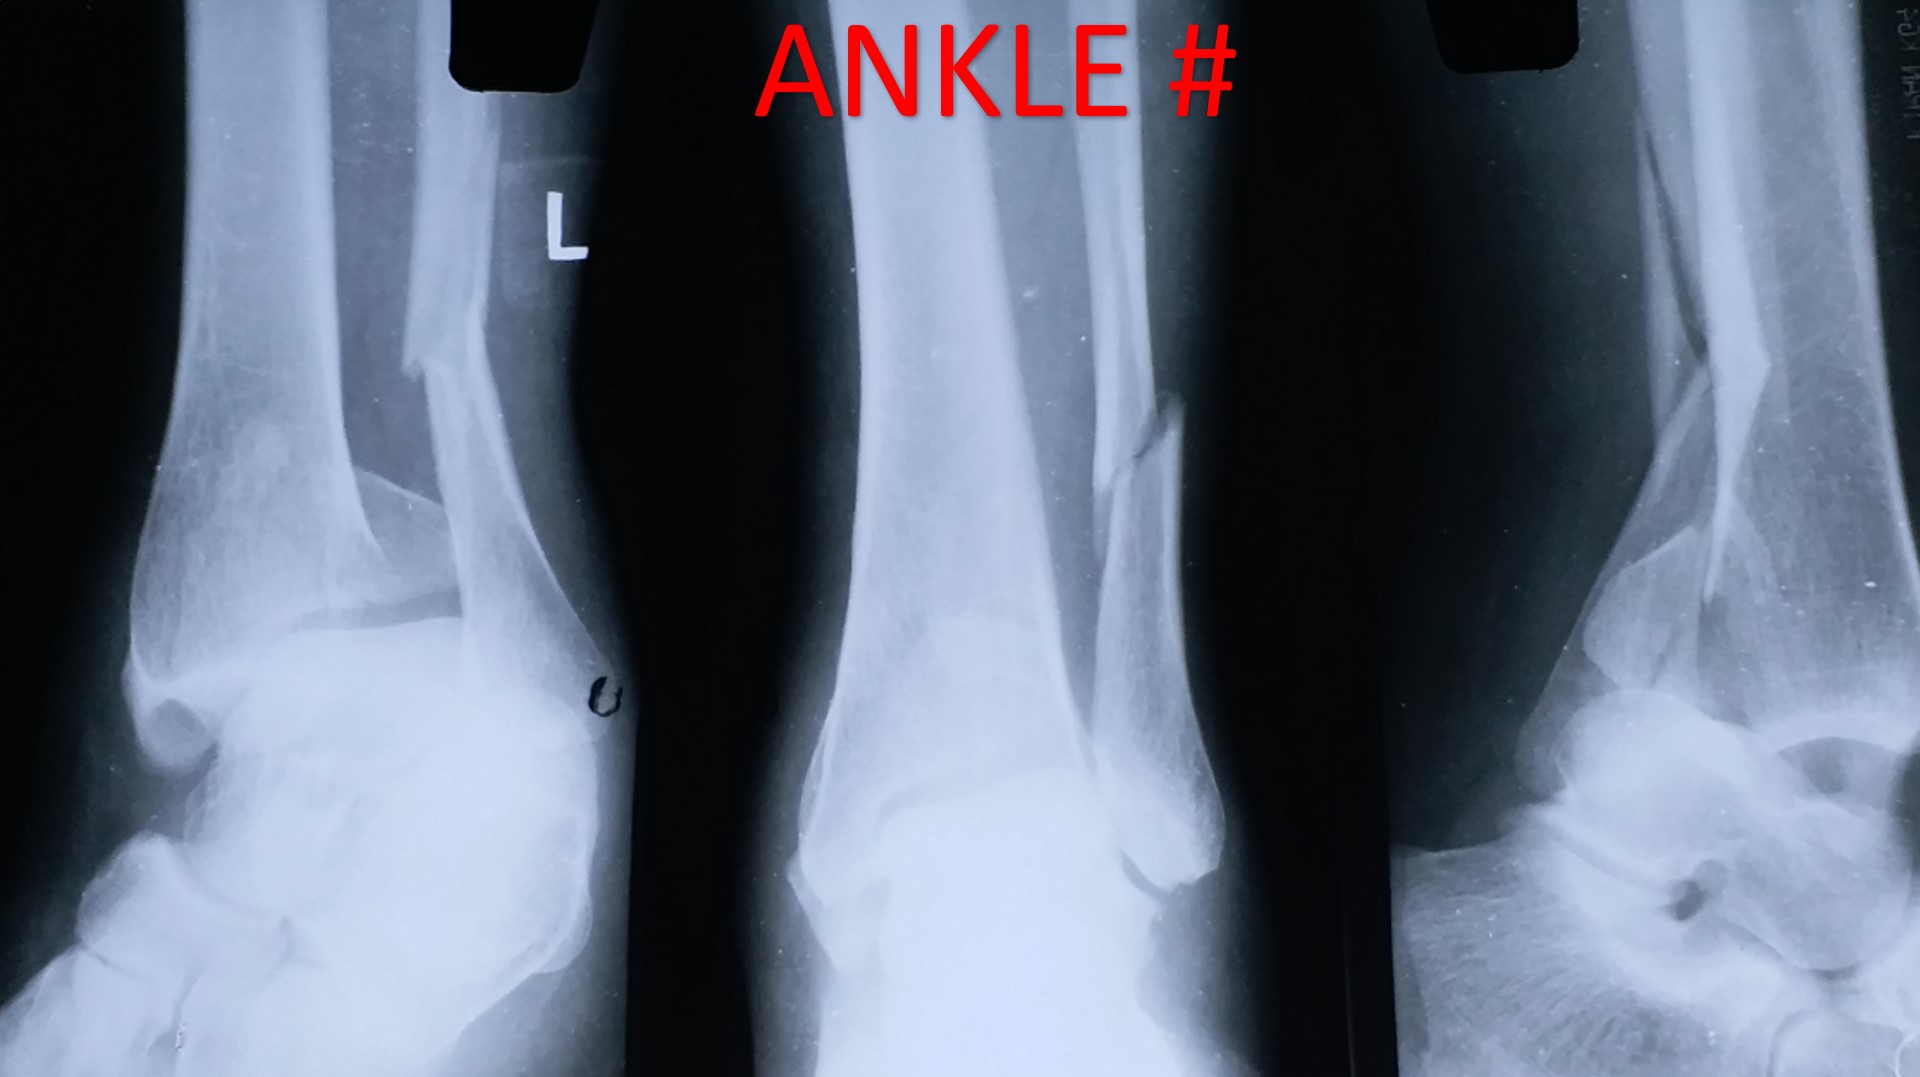

CRPP ( Closed Reduction Percutaneous Pinning )

• Most of the metaphyseal fractures of both upper and lower limbs can be successfully treated by CRPP.

• It can be applied to any intraarticular fractures, distal end radius, elbow, ankle and foot.

• It can be applied safely in fractures, where ORIF (Open Reduction Internal Fixation ) cannot be performed or postponed due to impending soft tissue complications.